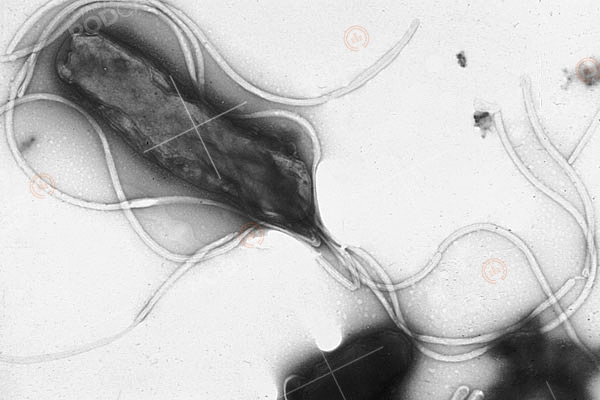

แต่ยังมีสิ่งมีชีวิตชนิดหนึ่งที่เป็นตัวกระตุ้นให้เกิดโรคกระเพาะอาหารอักเสบ คือ เฮลิโคแบคเตอร์ ไพโลไร (Helicobacter Pylori) เรียกกันสั้น ๆ ว่า เอช. ไพโลไร (H. Pylori) แบคทีเรียชนิดนี้ลำตัวจะกลม ๆ ยาว ๆ คล้ายหนอน และมีหนวดยาว ๆ คล้ายหมึก เมื่อเข้าไปอยู่ในกระเพาะอาหารที่มีแต่น้ำย่อยซึ่งมีคุณสมบัติเป็นกรด ส่วนใหญ่แล้วเชื้อแบคทีเรียจะตายแต่ชนิดนี้กลับไม่ตาย เพราะมีความสามารถในการผลิตด่างเพื่อป้องกันตัวเอง จึงสามารถต้านทานความเป็นกรดของน้ำย่อยได้เป็นอย่างดี แบคทีเรียชนิดนี้เมื่อเข้าสู่กระเพาะอาหารแล้วจะไปแทรกฝังตัวอยู่ในช่องหรือใต้เซลล์ผิวของเยื่อบุกระเพาะอาหาร มีชีวิตยาวนานนับ 10 ปีโดยไม่แสดงอาการอะไรเลย แต่หน้าที่ของมันจะไปกระตุ้นการหลั่งของฮอร์โมนแกสตริน (Gastrin) แล้วฮอร์โมนตัวนี้ก็ไปกระตุ้นการหลั่งน้ำย่อยในกระเพาะอาหารมากขึ้น ทำให้กระเพาะอาหารขาดความสมดุลจนทำให้เป็นโรคกระเพาะอาหารอักเสบได้